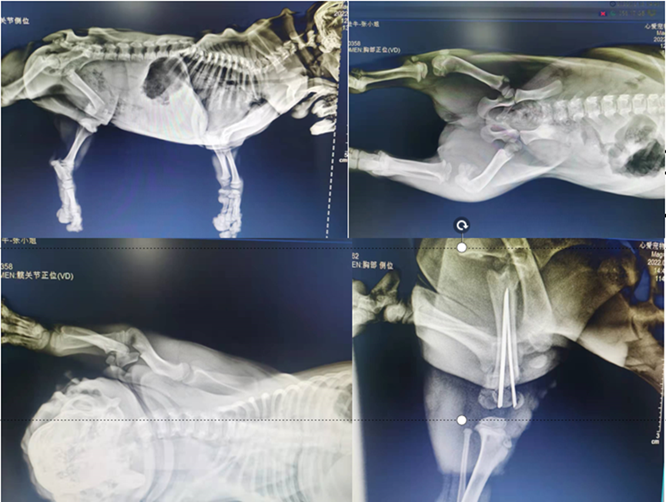

• 小黑X射线结果:小黑X射线结果如图3所示

小黑的X射线结果中可以看出,小黑左后肢以及左前肢骨折;从全血计数结果以及斯马特生化10项结果可以看出,小黑因坠地冲击导致肝脏有一定程度的受损。